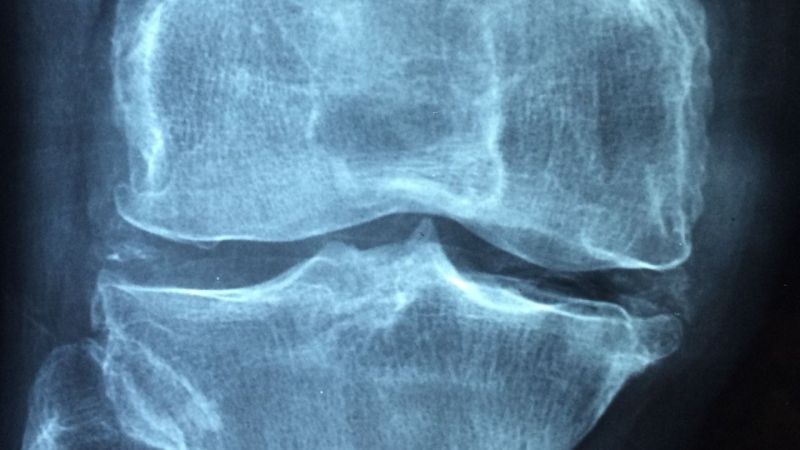

Op. Dr. Mesut Bolat, kök hücrenin aslında anaç bir hücre olduğunu, bulunduğu veya verildiği her dokuya dönüşebilme özelliğine sahip olan önemli bir doku olduğunu kaydederek, “Eklemlerde meydana gelen kıkırdak hasarları tamir edilerek onarılması kök hücre tedavisi ile mümkün. Günümüzde son derece popüler olan kök hücre tedavisi sayesinde kıkırdak gibi üretilmesi ve inşası zor olan dokuların yeniden yapılanma sürecinde farklı tedavi yöntemleri hastalara şifa oluyor” diye konuştu.

Şiddetli eklem ağrısı şikayetleri olan ancak cerrahi için erken veya ameliyat olmaktan çekinen ortopedi ve travmatoloji hastalarında, kireçlenme sürecinin ilerlememesi ve kıkırdakların daha hızlı iyileşmesini sağlamak için kök hücre tedavisine başvurulduğunu anlatan Dr. Bolat, “Bu tedavi şekli, kas, bağ ve menisküs yırtıkları gibi şikayetlerde etkili bir yöntem olarak öne çıkmaktadır. Bu yüzden etkili bir yöntem olarak tercih edilir” diye konuştu.

Op. Dr. Bolat, kök hücre işleminin oldukça basit olup hastanın uygulamadan hemen sonra taburcu edilebildiğini ifade ederek, “Kök hücre yöntemi özellikle tüm eklemlerin kıkırdak kireçlemelerde, menisküs ve bağ yaralanmalarında, iyileşmeyen kemik kırıklarında, bel ve boyun fıtıklarında, diyabete bağlı yaralarda, yanık gibi yara izlerinin hasarlarında güvenle uygulanabilir” dedi.